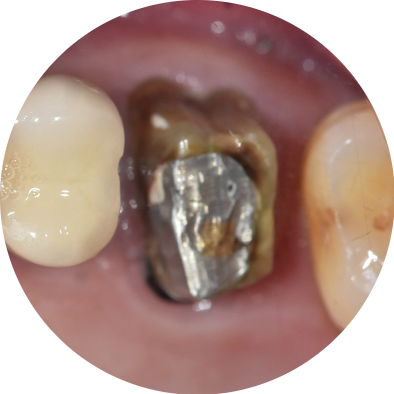

금니가 빠진 상태로 오래 방치하다 내원해 주신 환자분이 계셨습니다.

처음에는 빠진 크라운을 집에서 대충 끼우고 계셨대요.

250822 금니 빠진 후 치아 내부 충치가 진행된 모습

사진을 보시면 충치가 상당히 깊게 진행됐죠?

환자분도 처음에는 "그냥 붙여주세요!"라고 하셨는데, 며칠 다 다시 오셨어요.

"찬물 마실 때는 괜찮은데,

손만 가져다 대도 아파요..."

결국 이 환자분은 신경치료를 진행했고, 다행히 잘 마무리돼서 크라운치료까지 완료했습니다.